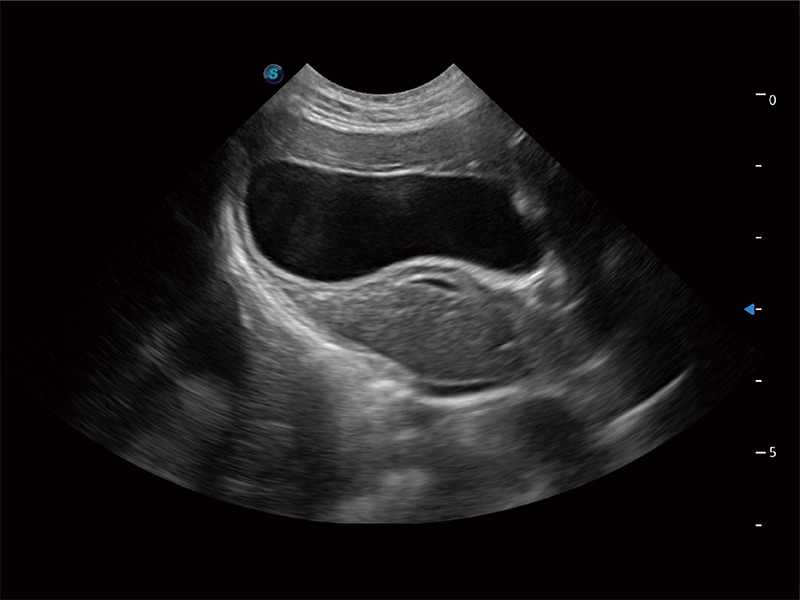

一鍵自動識別膀胱壁及自動測量膀胱容積,不受膀胱形狀和大小的限制,幫助醫(yī)生快速精準(zhǔn)獲得測量的數(shù)據(jù)。